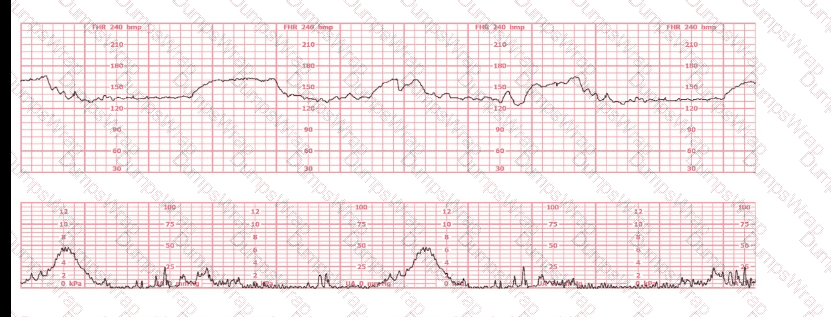

Based on the fetal heart rate tracing shown, the expected fetal pH would be:

Options:

Above 7.15

Below 7.15

Unaffected by the fetal heart rate

Answer:

AExplanation:

Comprehensive and Detailed Explanation From Exact Extract–Based NCC C-EFM References:

Assessment of likely fetal acid–base status is grounded in NCC-aligned principles that correlate fetal pH with fetal heart rate patterns, especially variability, presence/absence of accelerations, and type and depth of decelerations.

This tracing shows the following features:

Baseline:

The fetal heart rate baseline is approximately 140–150 bpm, within the normal 110–160 bpm range.

Variability:

Moderate variability is present—approximately 6–25 bpm amplitude.

Per NCC and NICHD definitions, moderate variability is strongly associated with normal fetal oxygenation and normal fetal pH > 7.20–7.25.

Accelerations:

There are occasional small accelerations, another strong indicator of normal fetal acid–base status.

Decelerations:

The tracing shows occasional variable decelerations, shallow and brief, recovering rapidly, typical of intermittent cord compression.

NCC references emphasize that intermittent, non-recurrent variables with moderate variability do not correlate with acidemia.

Uterine activity:

Contractions are present but not excessive, and fetal response remains reassuring.

Correlating tracing features with fetal pH (per NCC, AWHONN, Simpson, Menihan):

Moderate variability is the strongest intrapartum indicator of normal fetal pH.

The NICHD/NCC consensus repeatedly states that:

“The presence of moderate variability reliably predicts adequate fetal oxygenation and a fetal pH above the threshold associated with metabolic acidemia.”

Fetal pH below 7.15 is associated with:

Absent variability

Recurrent late decelerations

Recurrent deep variable decelerations

Prolonged bradycardia

None are present in this tracing.

Because the tracing demonstrates moderate variability, intermittent uncomplicated variables, and no recurrent late decelerations, the physiologic expectation is that the fetal pH remains normal, significantly above 7.15.

Therefore, the correct answer is: A (above 7.15).